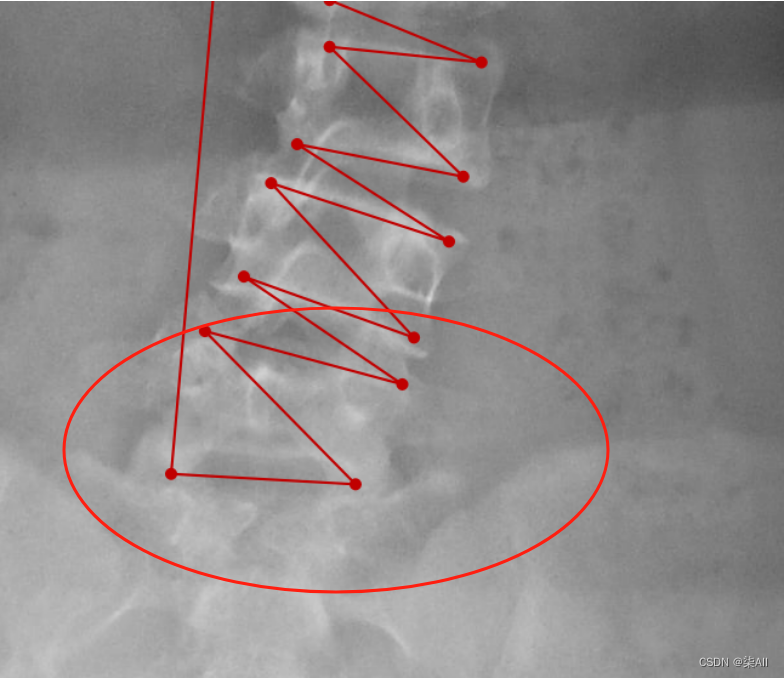

- (1)标注的椎体应该近似是一个矩形,而不是梯形 如下图

- 下图这个就不太行

(1)标注的椎体应该近似是一个矩形,而不是梯形 如下图

下图这个就不太行